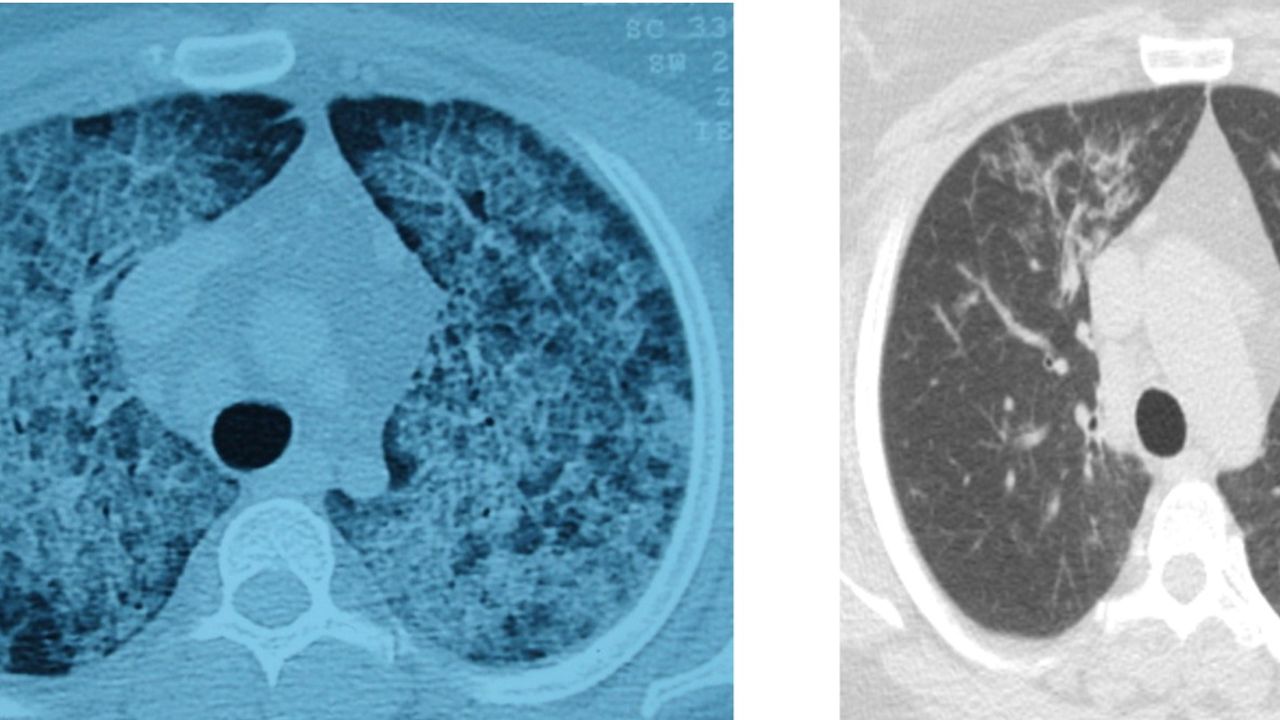

Hastalığın, kişinin kendi yağ ve proteinlerinin temizlenmesiyle görevli hücrelerdeki sorun nedeniyle akciğerlerdeki hava keseciklerinin birikmesi sonucu ortaya çıktığını aktaran Ergur, belirtilerin nefes darlığı, yorgunluk ve aşırı halsizlik olduğunu kaydetti.

Ergur, hastalığın çoğu zaman astımla karıştırıldığını, tanının ancak ileri tetkiklerle konulabildiğini ifade etti.